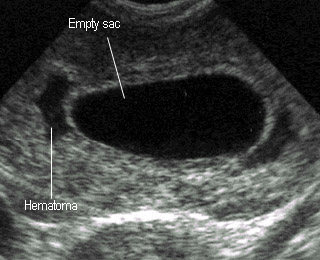

ท้องลม blighted ovum

ท้องลม ศัพท์ทางการแพทย์ คือ blighted ovum หรือ Anembryonic pregnancy หมายถึง การตั้งครรภ์ในโพรงมดลูกแต่ไม่มีตัวทารกในถุง การตั้งครรภ์มีแต่ถุงการตั้งครรภ์เปล่าๆเท่านั้น เชื่อว่าเกิดจาก การพัฒนาที่ผิดปกติ ทำให้ไม่มีทารกหรือทารกเสียชีวิตไปตั้งแต่ยังเล็กมากๆ

ทราบได้อย่างไรว่าการตั้งครรภ์ครั้งนี้ เป็นท้องลม

• ท้องลม สามารถตรวจพบได้จากการทำอัลตราซาวด์ ปกติการตรวจอัลตราซาวน์จะเริ่มเห็นถุงการตั้งครรภ์ ตั้งแต่ประมาณ อายุครรภ์ 5 สัปดาห์ เมื่ออายุครรภ์ 6 สัปดาห์ จะเริ่มเห็นตัวอ่อน และเห็นการเต้นของหัวใจ จาก การตรวจถ้าอายุครรภ์เกินสัปดาห์ที่ 8 ไปแล้ว แต่ดูแล้วไม่เห็น แพทย์ถึงจะวินิจฉันว่าเป็นท้องลม นอกจากนั้นแพทย์จะ ใช้วิธีวัดขนาดถุงการตั้งครรภ์ ปกติถุงตั้งครรภ์ขน าด 2.5 เซนติเมตร จะพบตัวอ่อนได้แล้ว หากตรวจไม่พบ สามารถ วินิจฉัยได้เลยทันทีว่า การตั้งครรภ์ครั้งนี้ เป็นท้องลม

• คนที่เป็นท้องลมจะเหมือนกันคนท้องปกติ บางคนไม่มีอาการเลยแต่มาตรวจพบว่าเป็นท้องลมจากอัลตราซาวน์ บางคนก็มีอาการของการแท้ง เช่น ปวดท้อง มีเลือดออก เมื่อไปตรวจจึงพบว่าเป็นท้องลม